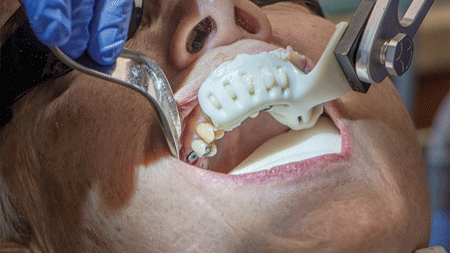

Researchers found that scaffolds loaded with strontium at any concentration stimulated wound healing A team of University at Buffalo researchers has developed a new strontium-loaded scaffold that can be personalized to fit any size dental implant and could help improve healing and tissue attachment in patients. The success of dental implants is dependent on the … Read more